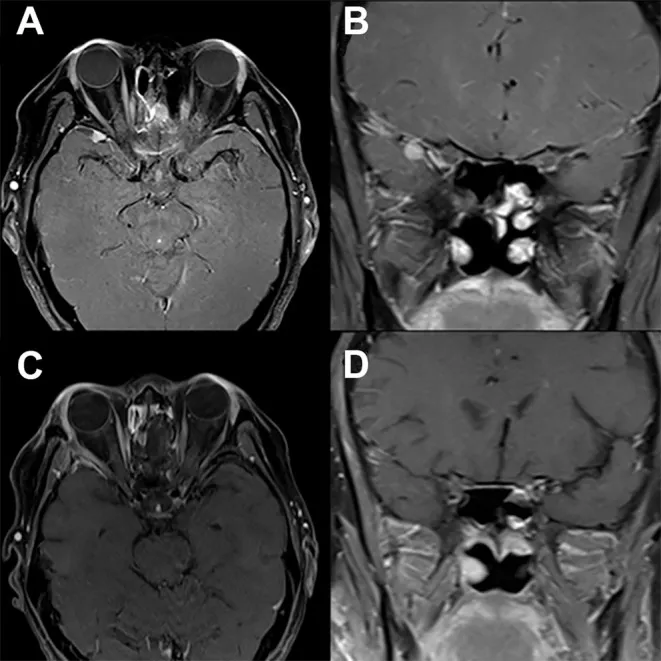

这是一例多年前曾行嗅神经母细胞瘤切除术的患者,术前轴位(A)与冠状位(B)T1加权钆增强MRI显示沿右侧蝶骨大翼新出现的均匀强化病灶。经右侧改良外侧眶切开眶-颅入路完整切除病灶后,术后轴位(C)与冠状位(D)T1加权钆增强MRI显示病灶已完全切除,患者神经功能完全恢复,无新增神经功能缺损。

图.改良外侧眶切开术案例分享